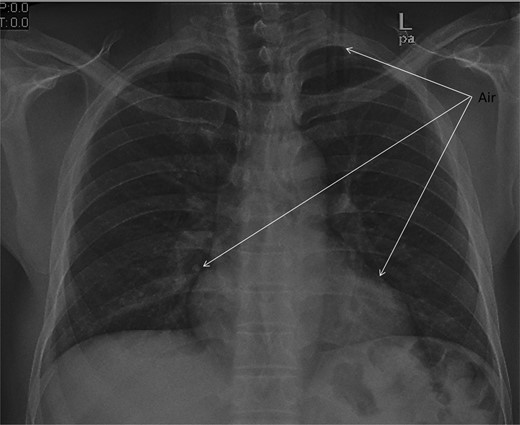

Chest X-ray and head, neck and chest computed tomography (CT) confirmed the diagnosis and extension of PM (Figs 1–3). CT revealed fracture of the floor of left orbit with soft tissue, fat herniation into left maxillary sinus roof, left orbital emphysema with no muscular entrapment. Gas was observed in periorbital tissues, left temporal scalp, infratemporal fossa, left parapharyngeal space and left cheek. Moreover, tissue planes in the neck revealed the presence of air particularly around the carotid vessels, in the posterior triangle and superior mediastinum (PM) around the thymus, trachea (middle), left side of the aorta and anterior to the sternum. However, on auscultation, lungs were clear with and the laryngeal passages and trachea looked normal.

Different levels of head imagining showing fracture of the floor of the orbit and subcutaneous air.